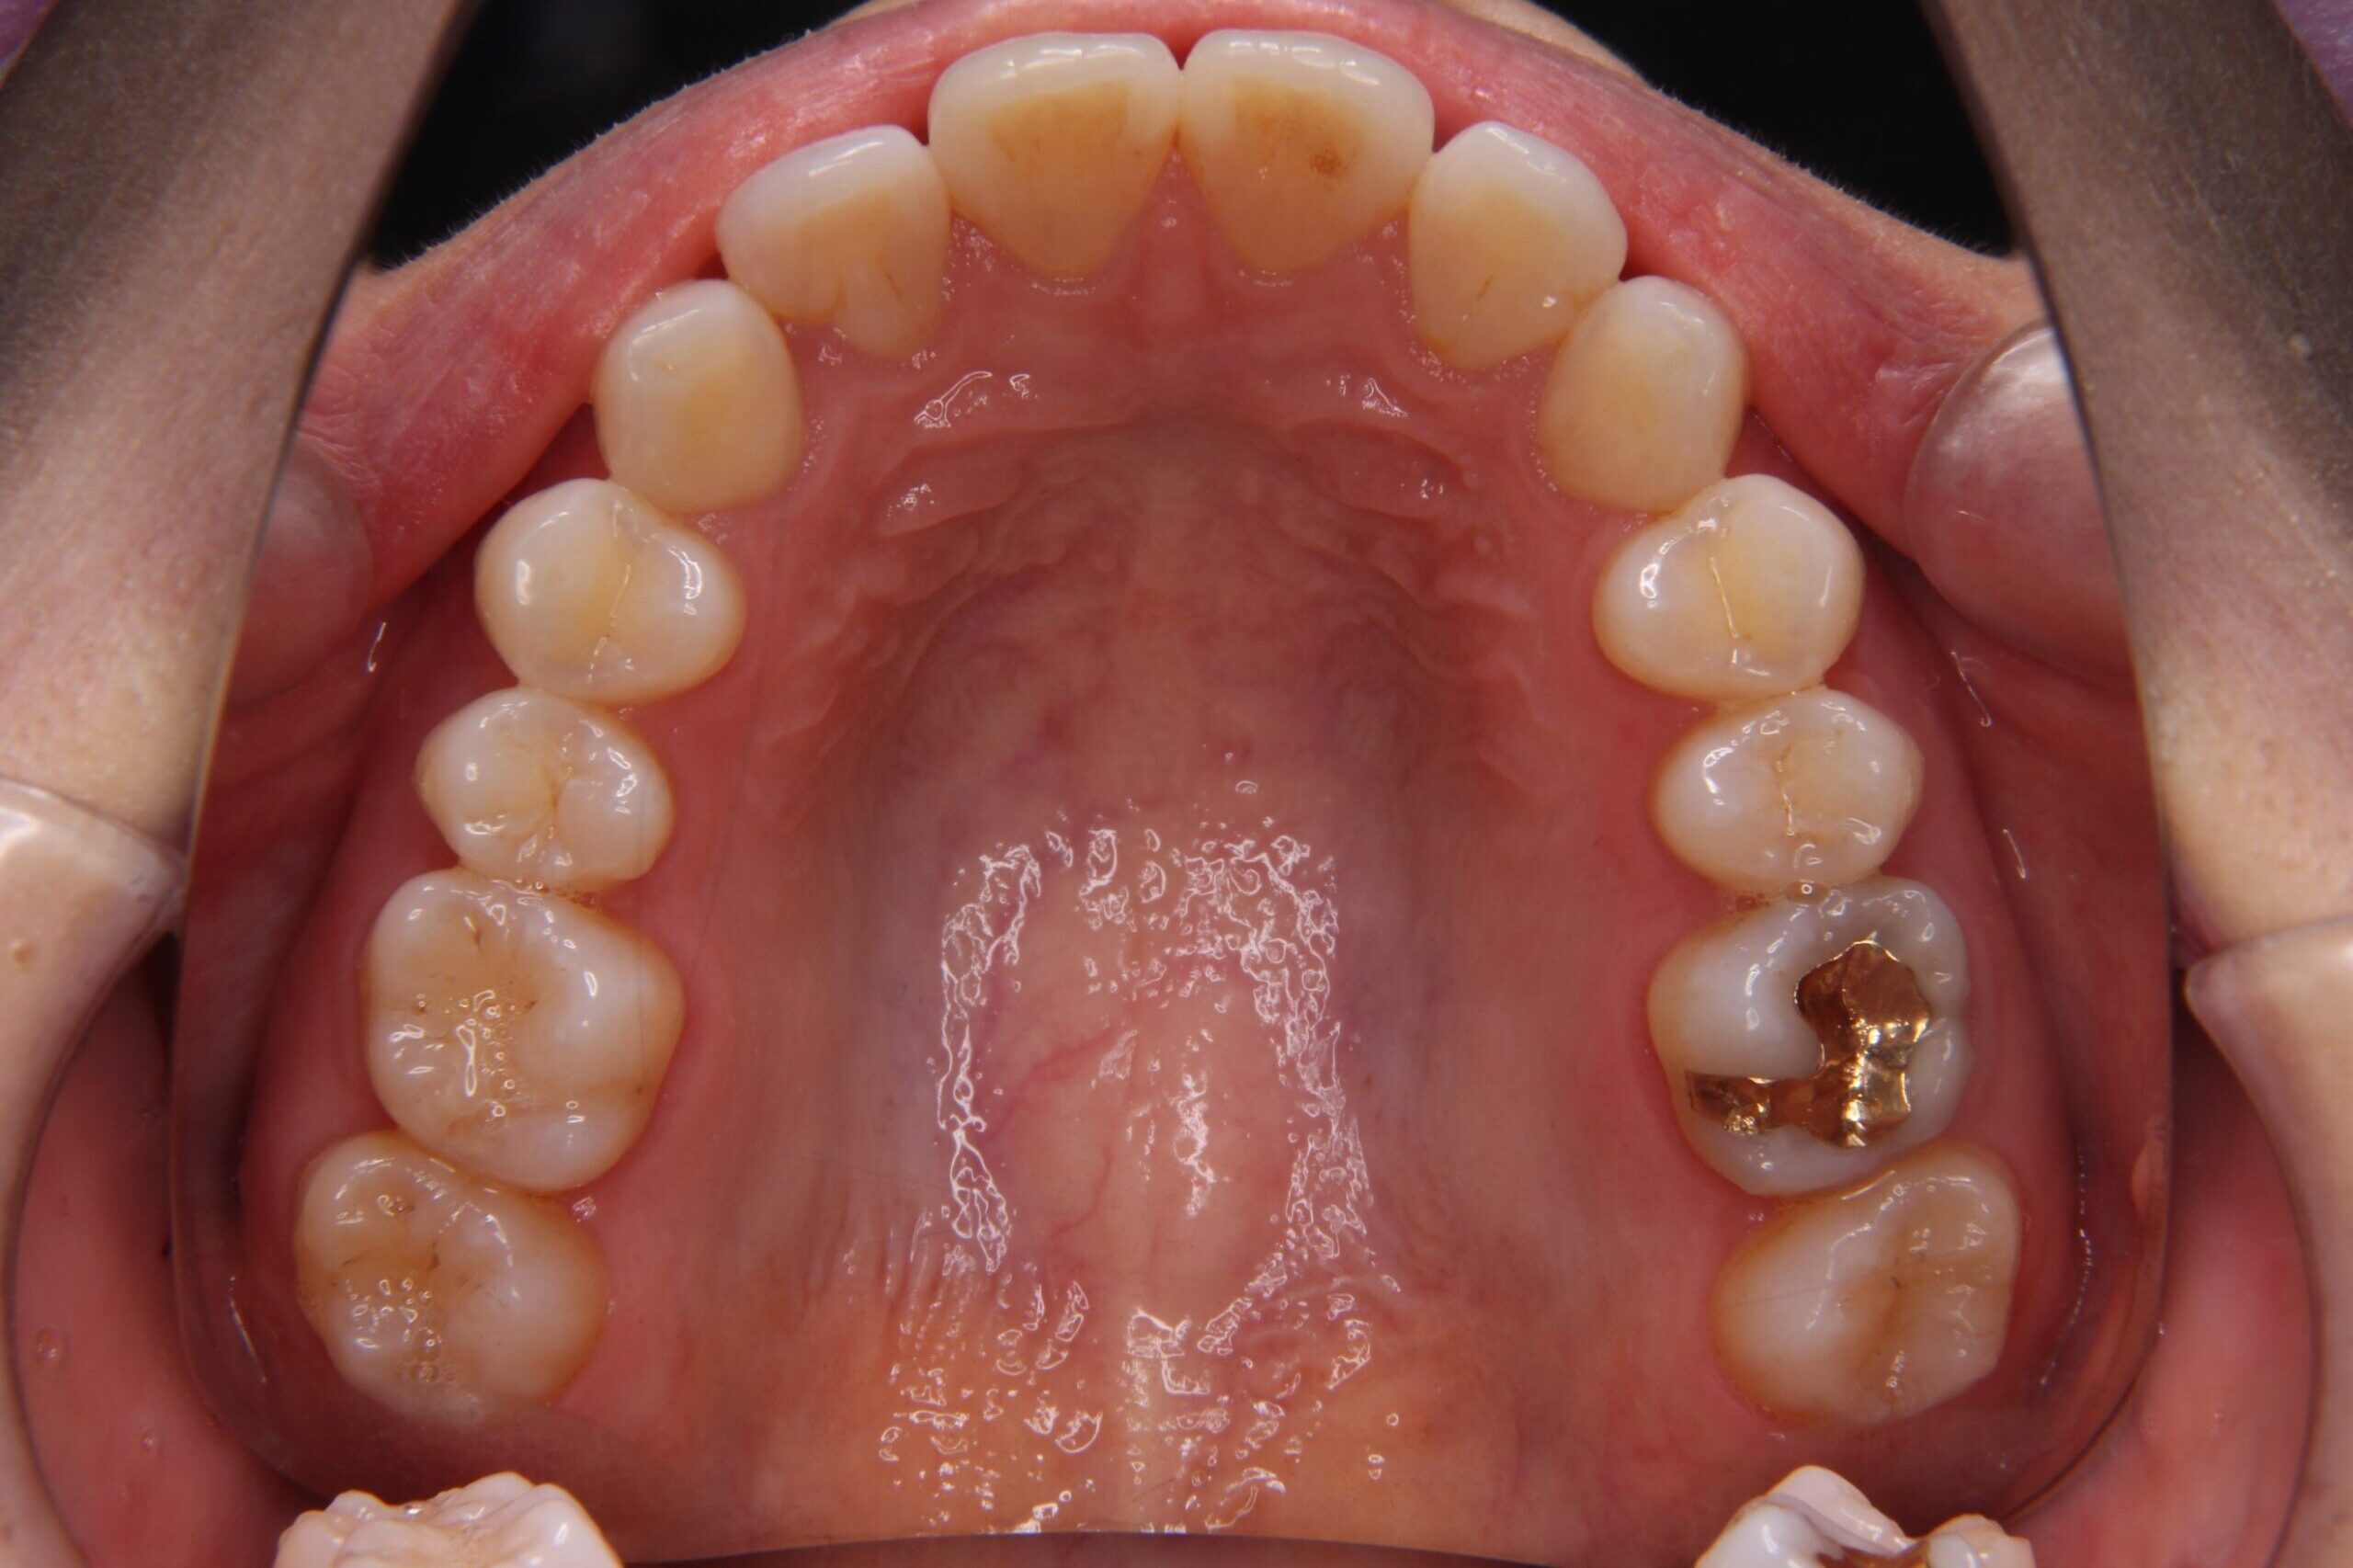

インビザライン矯正前

インビザライン矯正を実際にスタートするにあたり、まず行うこととして、アタッチメントと呼ばれる歯の表面にレジンの突起物を付けます。

これを付けることで、歯に加わる力を調整し、歯を効率的に動かすことができます。

アタッチメントには、実は様々な形状があり、歯を動かしたい場所や動かし方によって、形状、数、場所が変わってきます。

どこの場所にどのような形のアタッチメントを付けると、効率よく歯が動かせるのか、とても考えられているんです(*^^)v

しかも、白色なのでよく見ないと付いているのかもわからない程度で、

実際にアタッチメントを付けてもらうと、装着時はまったく痛みもなく、行うことができました!!

写真で見ると、こんな感じです↓↓↓